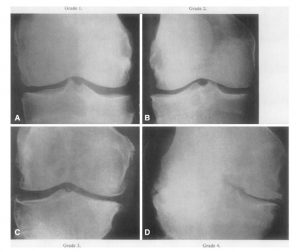

Gejala tersebut umumnya akan muncul secara bertahap. Lebih lanjut, penyakit ini terbagi menjadi empat tingkat keparahan. yaitu:

- Stadium 1, muncul benjolan kecil yang mengeras sekitar lutut (osteofit). Hal ini bisa menyebabkan kerusakan pada tulang rawan. Namun, rasa sakitnya belum terasa walaupun struktur sendi masih terlihat normal saat melakukan pemeriksaan dengan menggunakan sinar-X

- Stadium 2, benjolan osteofit mulai berkembang dan tulang rawan secara perlahan mulai menipis. Jaringan sekitar kemungkinan akan mengeras dan lutut akan mengalami kaku, terutama saat duduk.

- Stadium 3, tulang rawan mengalami kerusakan masif. Jaringan yang melapisi persendian perlahan mulai meradang dan membengkak, sehingga akan kesulitan untuk menekuk lutut, berjalan, dan lari.

- Stadium 4, ruang antara tulang dan persendian lutut semakin menyempit. Mengakibatkan, cairan sinovial sebagai pelumas alami menjadi berkurang. Kemudian, menyebabkan tiap gesekan antarsendi terasa sangat menyakitkan.